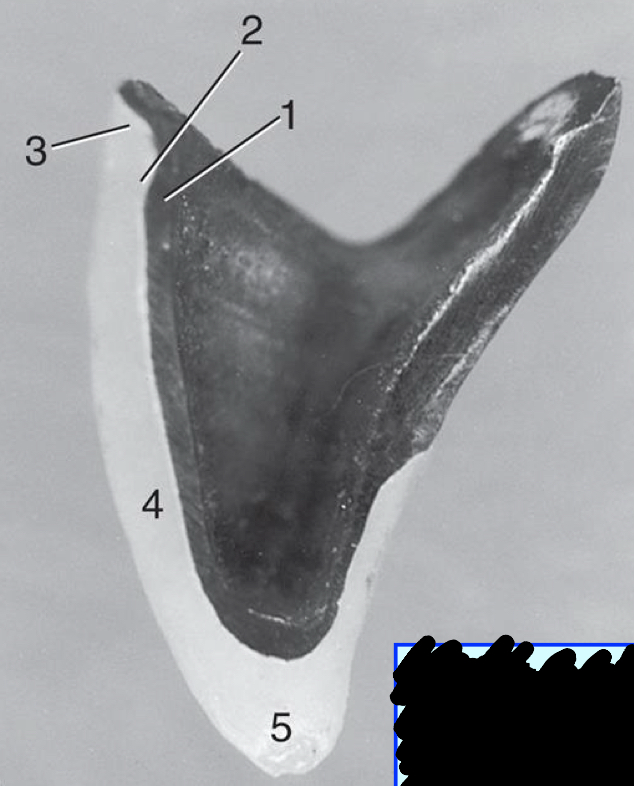

1

metal substructure

2

opaque porcelain

3

gingival porcelain

4

body porcelain

5

incisal porcelain